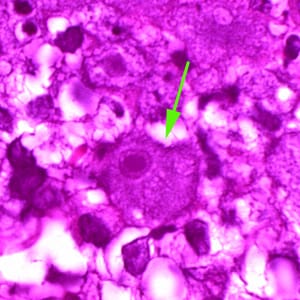

Balamuthia mandrillaris cysts.

The cysts of Balamuthia mandrillaris are highly similar morphologically to those of Acanthamoeba spp. and are also typically 10—25 µm (mean 15 µm) in diameter. Generally these cannot be reliably distinguished from Acanthamoeba spp. without either molecular confirmation or electron microscopy. The cysts have two walls apparent in light microscopy, and do not have pores: a wrinkled fibrous outer wall (exocyst) and an inner wall (endocyst) that may be variable in shape. A third layer (mesocyst) is only visible via electron microscopy. Cysts contain only one nucleus with a large karyosome. Cysts may be found in the brain, skin, lungs and other organs.

Balamuthia mandrillaris trophozoites.

Trophozoites of Balamuthia mandrillaris are pleomorphic and measure approximately 15—60 µm. They often produce long pseudopodia (broader than those of Acanthamoeba spp.). Trophozoites contain a large nucleus with a large, centrally-located karyosome but no peripheral chromatin. Binucleate forms are rare. There is no flagellated trophozoite stage in B. mandrillaris.